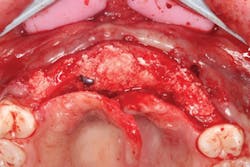

The patient was sedated intravenously in a surgically sterile in-office operatory. The surgical guide was placed over the teeth, checked to make sure it was fully seated without soft tissue impingement or surgical guide excess (figure 5). It was verified that there was no rocking of the guide from either side. An initial pilot drill was made through the guide into the soft tissue. A surgical incision was made with a 15c blade splitting across the keratinized gingiva across the crest of the ridge from Nos. 5–11. A full-thickness flap was elevated buccally and lingually. This released the soft tissue enough to allow the implant drills to go to depth and perform a widening osteotomy. Five osteotomies were made with copious saline irrigation and drill speed of 2,000 rpm. A pilot drill and each sequential step drill guide were used to widen out the osteotomy before placing five 3.5 mm x 10.5 mm MegaGen AnyRidge implants (figure 6). The implants were placed and torqued out at 35 Ncm. (Implants were not placed through the guide, although this was an option. Cover screws were placed. A bone graft with fusion bone binder (figure 7) and platelet-rich fibrin (PRF) were all placed over the implants before suturing with 5.0 polyglycolide sutures (figure 8). The upper partial was relined to take pressure off the soft tissue site.

Figure 8: PRF tucked into buccal and lingual tissues